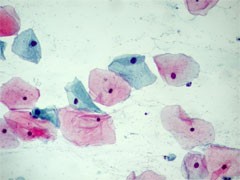

- Exfoliatives Zellmaterial vom inneren und äußeren Muttermund des Gebärmutterhalses wird mit Hilfe einer Bürste vom Gynäkologen entnommen und auf einen Objektträger ausgestrichen. Wichtig hierbei ist eine schnelle Fixierung der Zellen mittels Fixationsspray. Im Zytologischen Labor werden die Zellen mit der Papanicolaou-Färbung angefärbt und nach der Münchener Nomenklatur III befundet.

Unaufälliges Zellbild Gruppe I